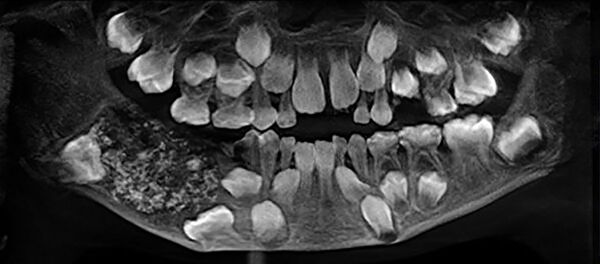

Kramtomosios gumos kontraindikacijos yra įvairios periodonto patologijos, tai yra, jei žmogus turi klibančių dantų, tada produktas tikrai nebus naudingas, be to, žmonėms, turintiems sutrikusią kramtomųjų raumenų funkciją, kramtomosios gumos nepatariama vartoti, paaiškino Bondarenka.